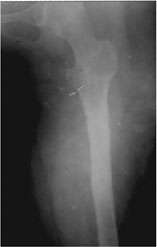

| The final x-ray picture 6 weeks after fixator removal. The regenerate has healed and remodeled well. The pin sites have also healed well. The regenerate would get recanalized in another 2 months time. |